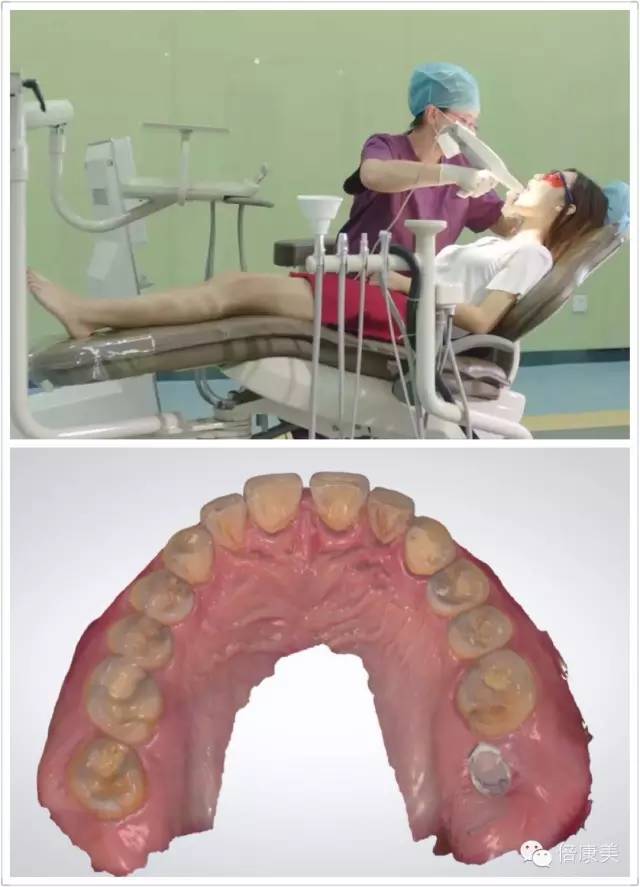

3shape数字化印模解决方案,不仅促进了诊所的发展,让我们变得更专业,同时它帮助我们朝着一个新的方向继续拓展我们诊所的业务。当然,这个新技术也引起了患者的关注,给他们留下很深刻的印象,所以患者时常会提出一些问题。患者很喜欢听到自己所接受的治疗设备和技术是在目前诊所中最先进的。

超高清全真彩扫描还原口内真实情况

无接触式光学取像,避免了传统的硅橡胶取模对软组织的压迫